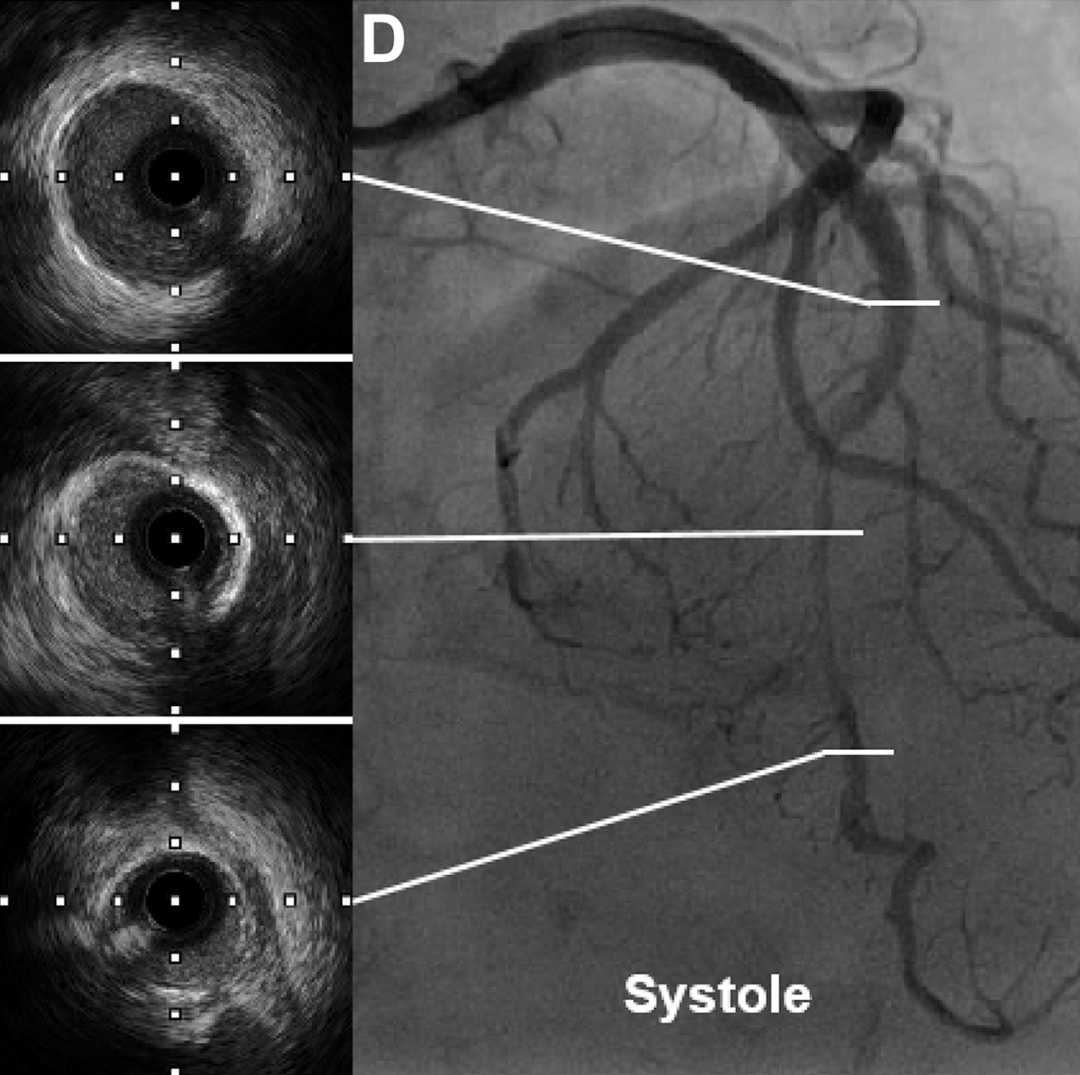

冠状动脉造影显示前降支存在孤立性心肌桥,伴有典型的 "挤奶现象";冠脉内注射硝酸甘油后,该效应加重(图C 和D)。其他心外膜动脉未发现狭窄。进一步的IVUS显示在出现"挤奶现象"的节段存在 "半月现象",这是心肌桥的典型特征。通过 β 受体阻滞剂(琥珀酸美托洛尔 23.75mg,每日一次)和抗焦虑药物(盐酸舍曲林片 50mg,每日一次)治疗,患者症状得到缓解。

(图C和D)舒张期和收缩期前降支的典型冠脉造影及对应IVUS图像。